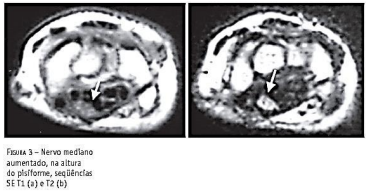

A partir dos conhecimentos de anatomia e fisiologia

o fisioterapeuta desenvolve a capacidade de avaliar e

corroborar situações e hipóteses diagnósticas que se

tornam muito importantes para a conduta profissional.

Por exemplo, conforme a imagem mostrada nesta

questão pode-se inferir que o possível diagnóstico e um

teste clínico que pode ajudar a comprovar tal suspeita

seriam respectivamente: